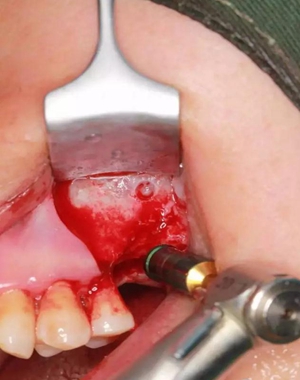

改良式外提升工具盒-外提 科貿(mào)嘉友收錄

六個(gè)月之后